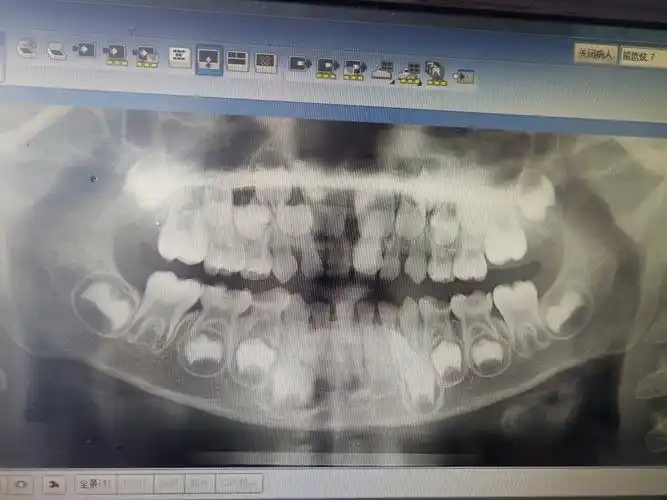

呈反颌状态,右上乳中切牙未脱落,无明显松动度,左右上颌侧切牙已替换

孩子今年7岁,这是在诊所拍的片子,哪位内行人能帮忙看看这个上中切牙